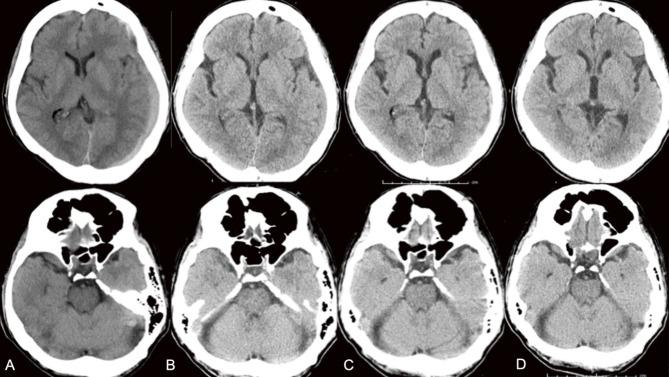

Chronic subdural hematoma (CSDH) in posterior fossa is rare, and its pathogenesis and treatment remain unclear. In this study, we report a case of a patient with CSDH in the posterior fossa who was taking warfarin and underwent middle meningeal artery (MMA) embolization successfully. A 59-year-old man taking warfarin for a mechanical aortic valve presented with a complaint of hearing impairment. He then developed headaches and was referred to our hospital after the previous physician identified CSDH above and below the left tentorium cerebelli on computed tomography (CT). We conducted MMA embolization with n-butyl-2-cyanoacrylate while continuing anticoagulation therapy. Right after the day of the surgery, symptoms of hearing impairment and right hemiplegia immediately improved. He was discharged after 10 days of hospitalization and was able to walk independently. His symptoms disappeared 20 days after surgery. There was no recurrence 100 days after surgery. In this study, we experienced a case of a CSDH in the posterior fossa that was clinically improved by MMA embolization. MMA embolization is a useful option for nonspecific CSDH without interruption of warfarin therapy.

后颅窝慢性硬膜下血肿(CSDH)较为罕见,其发病机制及治疗方法仍不明确。在本研究中,我们报告了一例服用华法林的后颅窝CSDH患者,该患者成功接受了脑膜中动脉(MMA)栓塞术。一名59岁男性因机械主动脉瓣置换术后服用华法林,出现听力减退症状。随后他出现头痛,在之前的医生通过计算机断层扫描(CT)发现左侧小脑幕上下均有CSDH后,转诊至我院。我们在继续抗凝治疗的同时,使用正丁基-2-氰基丙烯酸酯进行了MMA栓塞术。术后当天,听力减退和右侧偏瘫症状立即改善。住院10天后出院,能够独立行走。术后20天症状消失。术后百日无复发。在本研究中,我们遇到一例后颅窝CSDH患者,通过MMA栓塞术临床症状得到改善。MMA栓塞术是一种在不中断华法林治疗的情况下,治疗非特异性CSDH的有效选择。